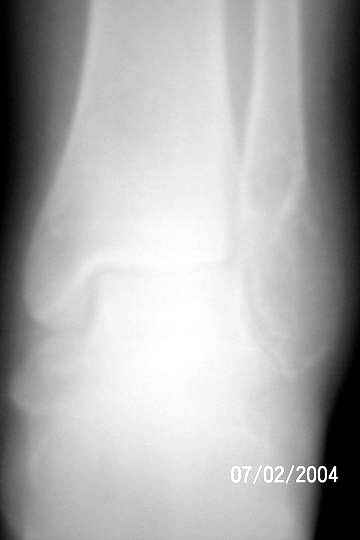

I am attaching an x-ray of 36 - years- old female patient had a cystic lesion with left fibula.

1 yrs back-curettage and bone-grafting elsewhere, for cystic lesion.

Biopsy report: Giant cell tumor – Grade 2